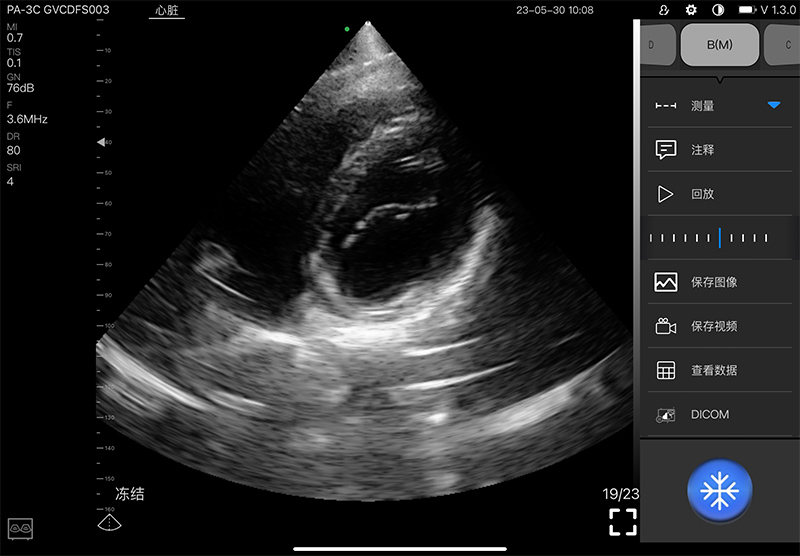

- Display mode: B, B/M, and Color, PW, CW, PDI

- Frequency: central 2.8MHz, cardiac reverse harmonic

3.6mhz, and the transcranial fundamental 2.2MHz